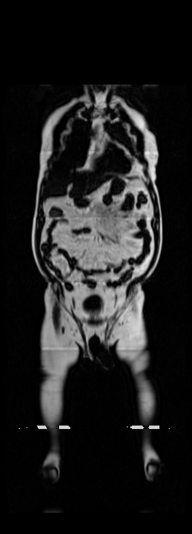

3.4 DXA to MRI Volume Generation

DXA is a single image data modality that is similar to X-ray but includes other non-bony information such as tissue mass [67]. It measures bone mineral density and body fat composition. The radiation level is low enough that it is acceptable for conducting studies of healthy participants, such as the UK Biobank. In order to leverage X-Diffusion to synthesize the MRI volume from a single DXA (as in Figure 3), they have to be aligned, and registered. Note that, the size of the DXA does not match the MRI () and the scans are not registered. The two modalities in UK BioBank were not taken simultaneously but close in time hence why we believe registration is feasible for these two sequences as illustrated extensively in [79].

In order to tackle this domain gap, we leverage a registration network [79] paired with a X-Diffusion to achieve DXA to MRI slice generation. [79] introduced a multi-modal image-matching contrastive framework, that is able to learn correspondences between DXA and middle coronal MRI slices. These networks extrapolate the DXA scan by a transform to the coronal MRI slice by harnessing the embedded patterns and features of the DXA and the coronal MRI mid-slice. X-Diffusion is then trained on the registered DXA () and corresponding MRI slices in () in the target MRI volumes and is able to produce precise MRI volumes that align with the DXA scans (see Figure 5 left). The other details are similar to Section 3.2 and Section 3.3.

Notably, X-Diffusion achieves state-of-the-art dB for a few input slices while baselines require more than 60 input slices to achieve similar performance (Figure 7). The margin is more than 12 dB PSNR for the 1-slice input in both the BRATS and the UK Biobank benchmarks (see Table 1 and Figure 6). For reference, two randomly sampled MRIs from UK Biobank would have a PSNR of 15.95 dB 0.36 (on 4800 randomly sampled examples). Omitting the preprocessing step of alignment DXA to MRI, leads to a drop of PSNR on average by 2.87 dB (29.01 dB 26.14 dB). The slices from 3D reconstructed volumes at varying depths and axis of rotation, visually match the ground truths for both brain and whole-body scans (see Figures 4 and 5 left). We also plot the error map (Figure 3) and the spread of the error (Figure 5 right) of such X-Diffusion generations to highlight the differences with the ground truth MRIs.